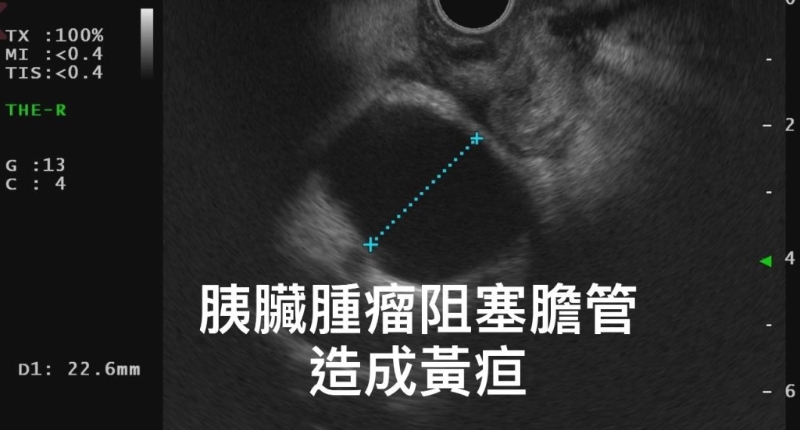

▲林相宏医生为男子进行超声波检查(图片获胃肠肝胆科医生林相宏授权转载)

后来其家人上网查找原因,意识到该男子可能是胰脏出了问题,遂再度求医。 林相宏医生为该男子进行胰脏内窥镜超声波检查,赫然发现其胰脏头部有一颗近4cm大的肿瘤,并已导致胆汁和胰脏阻塞。 林医生发现,该男子小便颜色深似浓茶,是明显的黄疸状况。林相宏医生提醒,上述症状全是典型胰脏癌的表现。